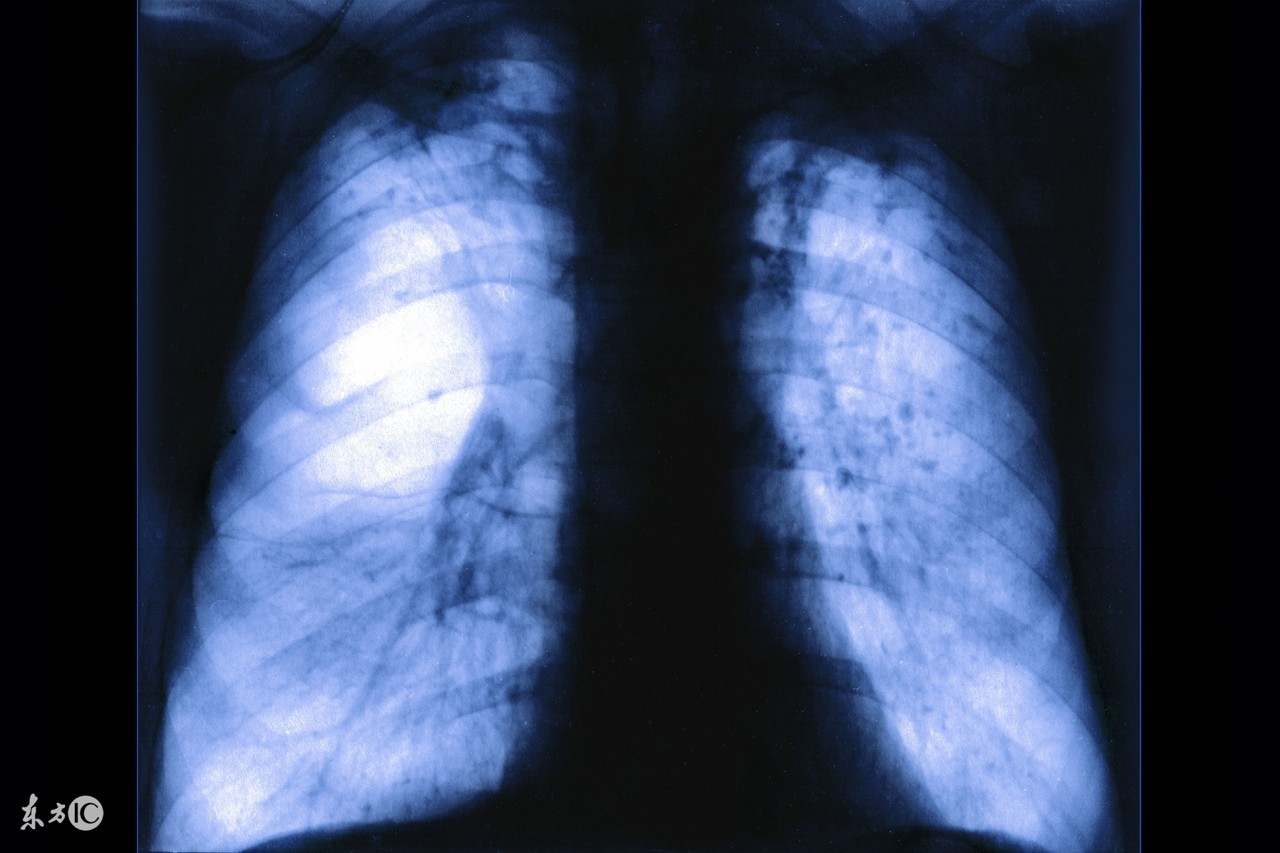

不少中老年人,不仅因此过早地丧失劳动能力,长期咳喘,痛苦万分,而且往往对病症悲观失望,有的甚至对人生丧失信心。其实,患有肺气肿的病人,如能进行合理运动,可以收到改善症状的明显效果。

老年人肺气肿怎么治